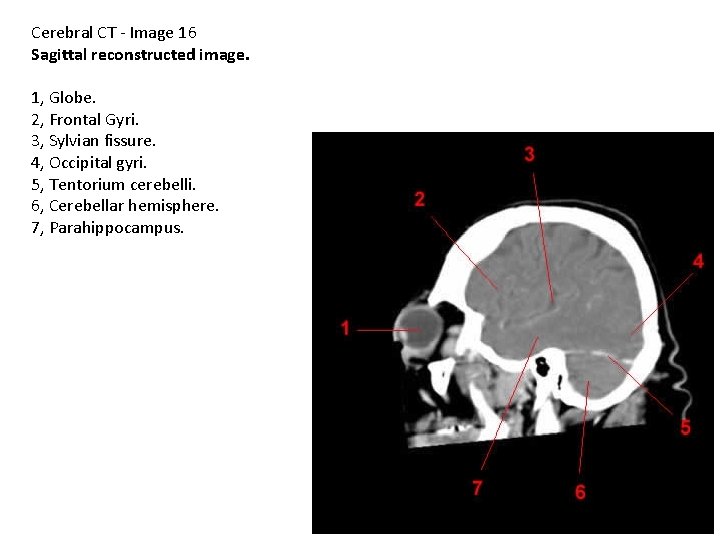

Cerebral CT - Image 16 Sagittal reconstructed image. 1, Globe. 2, Frontal Gyri. 3, Sylvian fissure. 4, Occipital gyri. 5, Tentorium cerebelli. 6, Cerebellar hemisphere. 7, Parahippocampus.